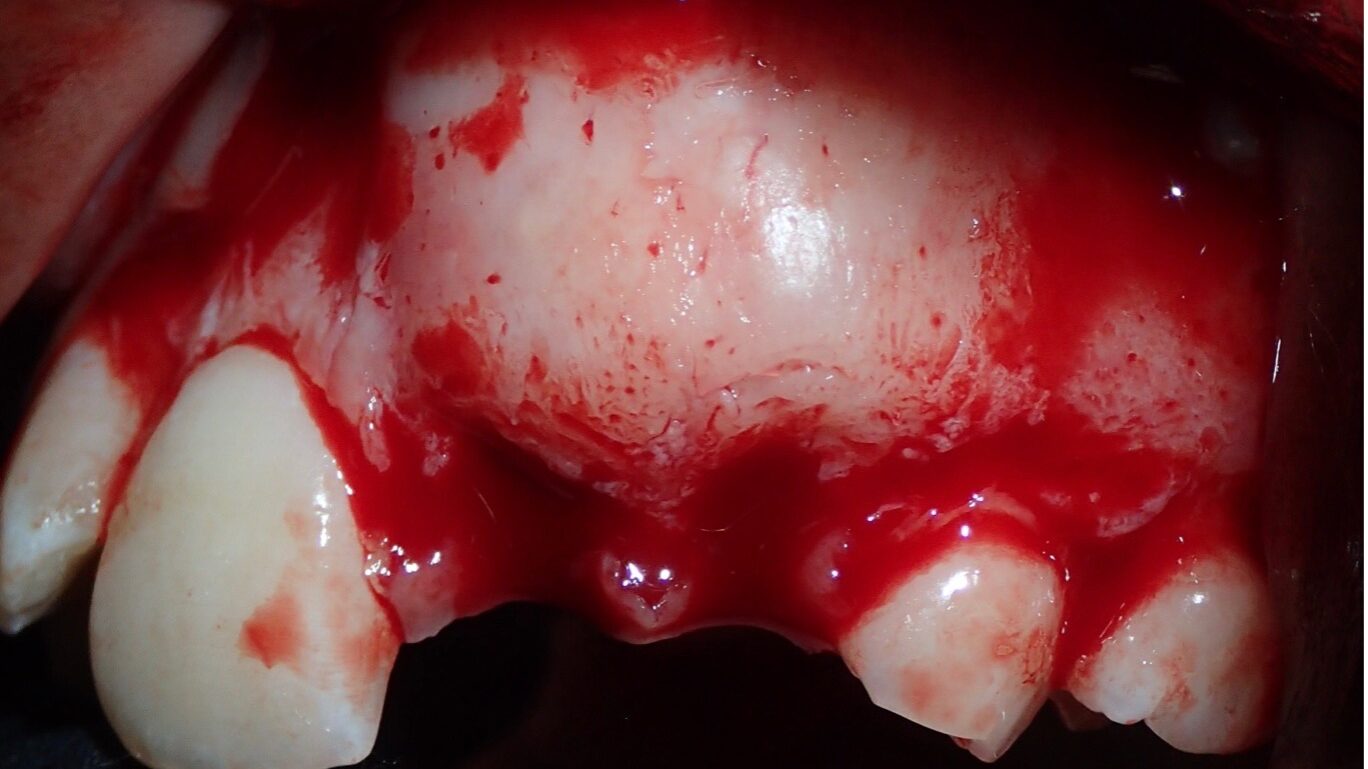

Abstract Stainless steel crowns or preformed metal crowns have become the standard for the restoration of primary teeth with extensive caries; however, they remain underutilized on permanent teeth. In this paper, we review the literature on the use of these crowns on permanent molars, and with the help of a case, discuss the indications, efficacy, … Read more